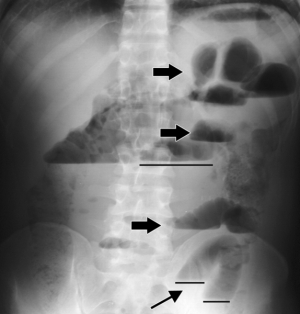

Κατά τον απεικομιστικό έλεγχο, σε περίπτωση απόφραξης λεπτού εντέρου, στην απλή ακτινογραφία κοιλίας σε όρθια έχουμε υδραερικά επίπεδα στις εντερικές έλικες που έχουν κλιμακωτή κατανομή. Το παχύ έντερο δεν περιέχει αέρα. Σε επιπλοκές διαπιστώνεται ελεύθερο υγρό ή αέρας (στη διάτρηση του εντέρου) ή υδραερικά επίπεδα εκτός των εντερικών ελίκων. Σε περίπτωση απόφραξης του παχέως εντέρου, στην απλή ακτινογραφία, το διατεταμένο παχύ έντερο, δίνει την εικόνα κορνίζας που πλαισιώνει την περιτοναϊκή κοιλότητα.Ο βαριούχος υποκλισμός συχνά χρησιμοποιείται για να δείξει το σημείο της απόφραξης.

Οι ακτινογραφίες που ακολουθούν δείχνουν απουσία αέρα στο ορθό και ευρήματα απόφραξης.

Βαριούχος υποκλισμός γίνεται για να διαπιστωθεί ή όχι απόφραξη στο παχύ έντερο.